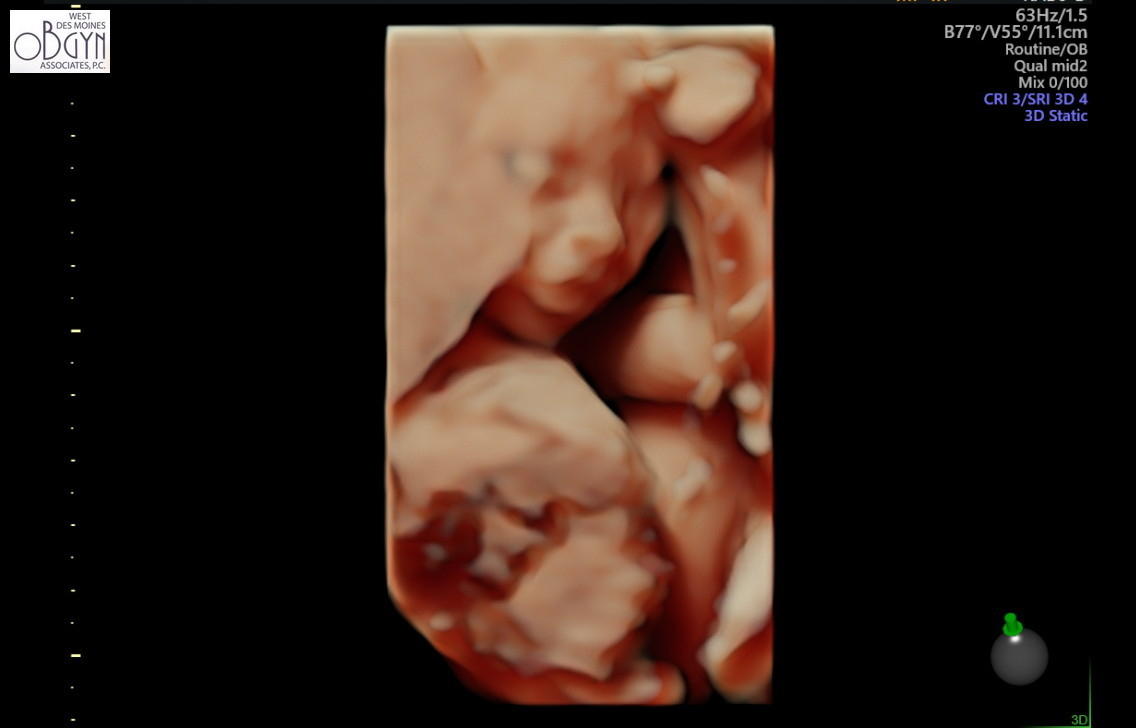

Bonus of a second scan in 3 days = I got 3D pics this time! Always a little creepy but this one is my favorite.

We had our follow up scan today to get the remaining pictures of baby girl's heart - all looks great, thank goodness! She's sucking her thumb here. She was still very active OR curled up in a ball and didn't want to move. Stubborn like her mama.